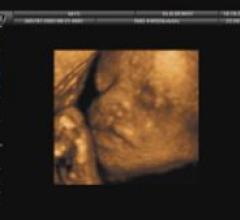

October 26, 2020GE Healthcare is highlighting artificial intelligence (AI) automation features on its Voluson Swift ultrasound platform at the 2020 Radiological Society of North America (RSNA) virtual meeting. Features of this system include semi-automated contouring, auto identification of fetal anatomy and positioning on imaging,

The new SonoLyst AI software can auto recognize 20 standard fetal views in the second trimester protocol. The goal is to speed exam times and make the exams more accurate, even for less experienced sonographers. The AI can tell users what any image is when they freeze the frame. This can be used to help cue up measurements and appropriate annotations. The AI also can tell th user if all the required anatomical structures are in an image needed for the exam protocols.